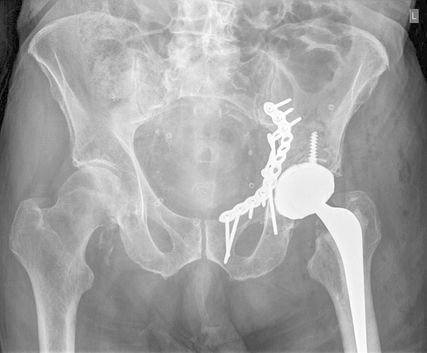

Die Mehrheit der Herausforderungen bei der Behandlung der Fragilitätsfraktur des Acetabulums überschneidet sich mit denen bei Beckenringfraktur. Ebenso wenig überraschend treten auch auf der anderen Seite des Hüftgelenkes ähnliche Komplikationen und eine Reduktion der Lebenserwartung wie bei hüftnahen Oberschenkelfrakturen auf. Im Unterschied zu den FFP gilt dieselbe Klassifikation für Hochrasanz- und Niedrigenergietraumata des Acetabulums nach Judet und Letournel. Der große Unterschied besteht jedoch in der Häufigkeitsverteilung. Aufgrund der meist einfachen Stürze mit Gewalteinwirkung über den Trochanter major betreffen die Fragilitätsfrakturen des Acetabulums meist den vorderen Pfeiler und die quadrilaterale Fläche. Entsprechend sind dislozierte Frakturen eine Domäne der offenen Operationsverfahren und der Hüftendoprothetik. Der Stellenwert der minimalinvasiven Stabilisierung nicht dislozierter Acetabulumfrakturen und der Stabilisierungen in Fehlstellung ist wissenschaftlich nicht geklärt. Jedoch gibt es zunehmende Literatur über das sogenannte „fix and replace“, bei dem eine Osteosynthese eines Pfeilers mit einer primären Totalendoprothese in einer Operation kombiniert wird (Abb. 2).

Abb. 2: „Fix and replace“ mit Osteosynthese und Hüfttotalendoprothese in der selben Operation bei geriatrischer Acetabulumfraktur mit Impressionsfraktur des Doms

Bisher konnten dabei keine erhöhten Komplikationsraten gegenüber der konventionellen Osteosynthese festgestellt werden. Gleichzeitig besteht aber der Vorteil der Vollbelastbarkeit, des Einsatzes einer konventionellen Pfanne und der in der Orthogeriatrie erwünschten „one-shot surgery“ (nur eine Operation statt einer potenziellen zweiten Operation bei Versagen der Osteosynthese und sekundärer Prothese). Bei ca. 30% der geriatrischen Acetabulum-Osteosynthesen in der Literatur erfolgte eine Revision mittels Prothese. Risikofaktoren für die Notwendigkeit einer sekundären Hüfttotalendoprothese nach Osteosynthese sind: höheres Alter, Impressionsfrakturen des Doms und Hüftkopfes, Medialisierung des Hüftkopfes („zentrale Hüftluxation“), nichtanatomische Reposition (häufig durch späte Versorgung nach konservativem Therapieversuch oder längerer Operationsvorbereitung bei Multimorbidität).

Im Gegenzug dazu wird in der Literatur auch eine minimalinvasive offene Osteosynthese beschrieben, wobei man auf ausgedehnte Repositionsmanöver mit dem damit verbundenen Blutverlust verzichtet. Dadurch werden zum Teil verbliebene Fehlstellungen akzeptiert bzw. wird durch postoperative Mobilisierung eine sekundäre Dislokation in Kauf genommen, um eine postoperative Vollbelastung zu ermöglichen. Eine entsprechende Operationstechnik über einen Stoppa-Zugang und mit Plattendesign mit Abstützung der quadrilateralen Fläche wurde durch Culemann 2023 anschaulich beschrieben.12 Bei geschwächter Knochenqualität ist neben dem Plattendesign mit medialer Abstützung an der quadrilateralen Fläche auch das Augenmerk auf eine stabile Verankerung zu legen. Die infraacetabuläre hintere Pfeiler-Schraube, welche meist um die 100mm Länge aufweist, ist hierbei sehr empfehlenswert (Abb. 2 und Culemann 202312).